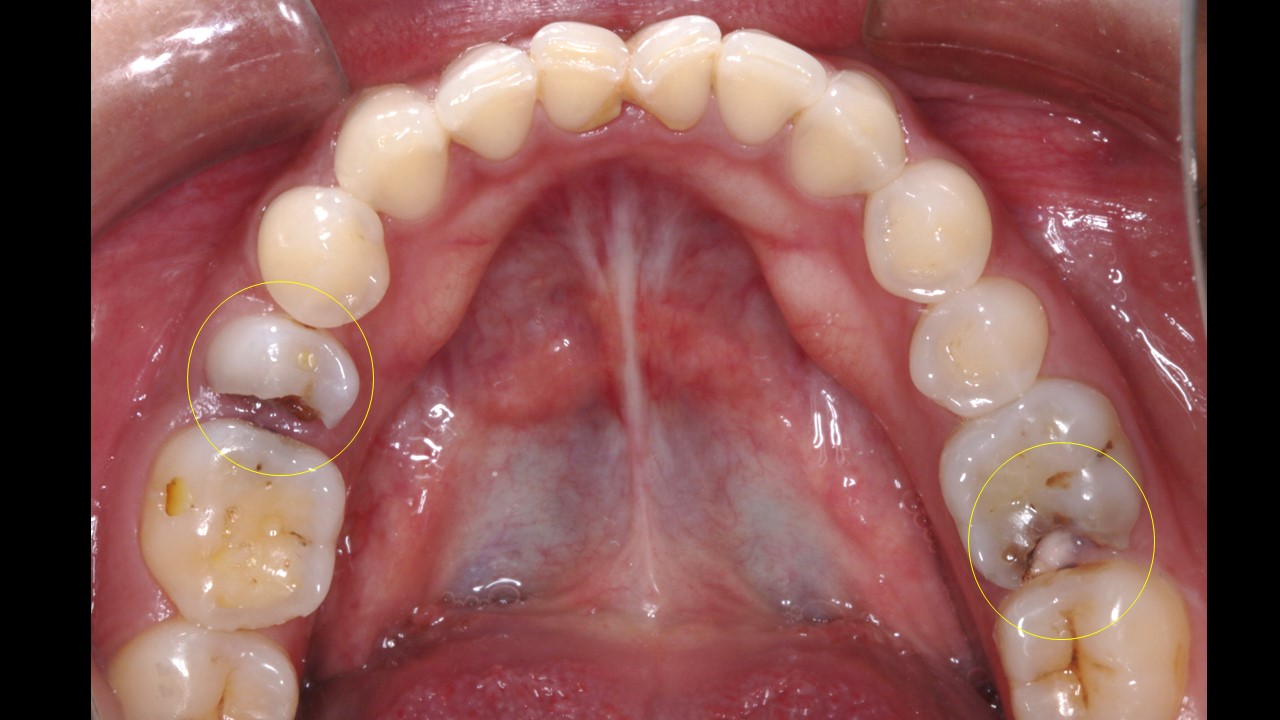

Mangement of decayed molar and premolar teeth.

Patient presented with pain and discomfort in the lower right second premolar. Pain was of radiating type accompanied with food lodgement. On examination, the lower right 2nd premoalr was decayed with a portion of the distal surface lost due to the process of deacy. Examination alos revealed decay of the molar on the mesial side. Typical presentation that accompanies food lodgement and decay.

Incidentally the 1st molar on the left side was also decayed , with pulpal invovement requiring intervention.